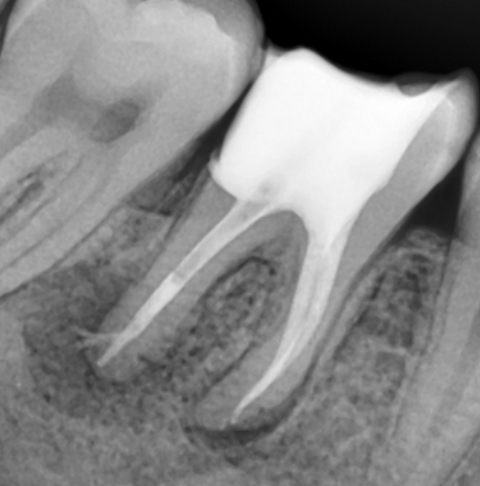

Mulți dintre dinții tratați sau retratați, sunt infectați sau prezintă o leziune inflamatorie periapicală (Fig. 4.9.6), de aceea evoluția cazului spre succes depinde foarte mult de îndepărtarea microorganismelor din sistemul canalar. Irigarea copioasă ne ajută, mai ales în cazul canalelor curbe și pentru a evidenția, curăța și obtura și anumite canale secundare ce sunt blocate de resturi dentinare (Fig. 4.9.7). Astfel, se reduce flora microbiană din sistemul canalar și din țesuturile adiacente favorizând vindecarea osoasă, situație observată după 6 luni în acest caz. (Fig. 4.9.8)